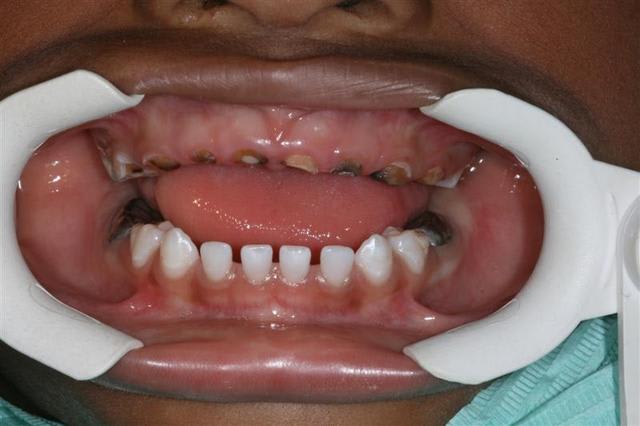

antoine, vs vs souvenez?(photo1)

le voilà 2 ans plus tard à 6 ans, tjours avec ses CP (comme quoi ça tient ces petites choses là)qqes dents en plus,tjours ses racines traitées qui lui servent de mainteneurs en anterieur

et mme... il se brosse bien les dents!

on peut gérer un enfant polycarié et motiver ses parents à venir ts les 6 mois et enfoncer et réenfoncer le clou de l'hygiène et prophylaxie et prevention tout comme je le fais auprès des eugenoliens:)